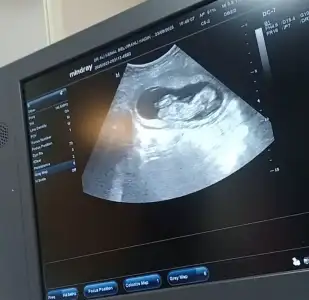

Banada tahminde bulunabilir misiniz? Kendi doktorum erkeğe benziyor başka bir doktor kıza benzettiği söyledi